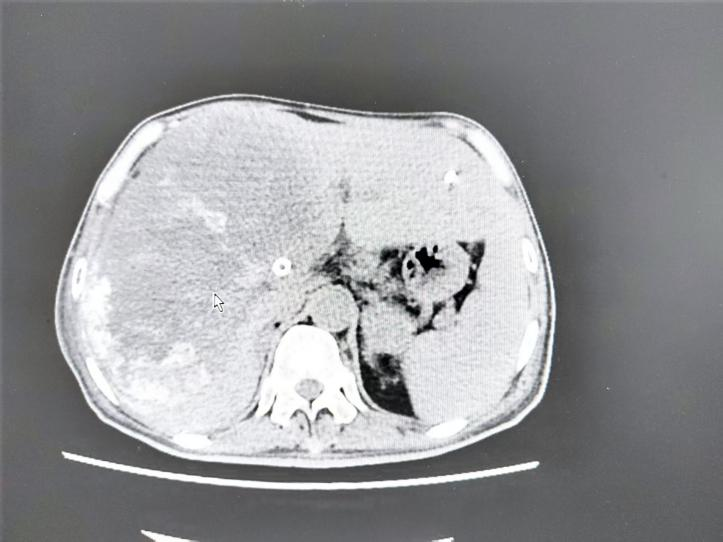

2025年9月29日CT示: